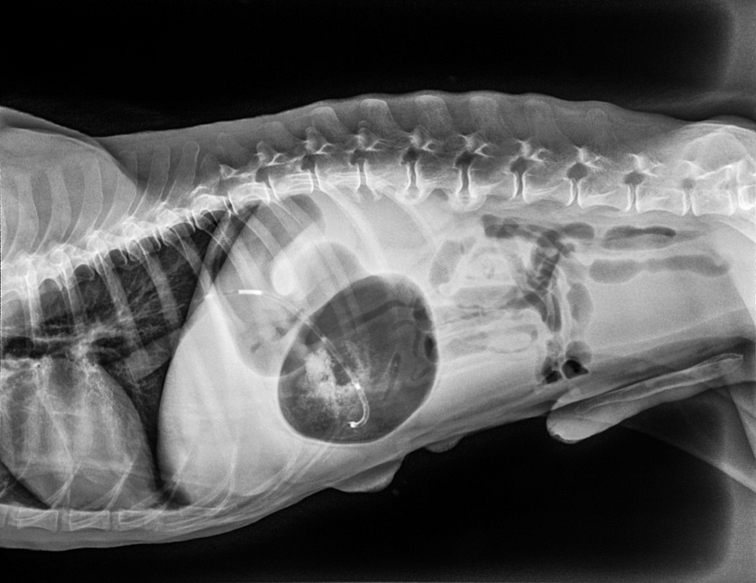

žalúdok sa roztiahne a otočí o 180–360 stupňov. Tým sa uzavrú vstup (otvor z pažeráka) a výstup (otvor do dvanástnika, lat. duodenum). Plyn spolu s obsahom žalúdka sa nemôže dostať von a hromadí sa tam.Tlak na cievy a orgány

žalúdok tlačí naánicu (zhoršenie dýchania), čo bráni návratu krvi k srdcu dolnou dutou žilou. Dochádza k šokovému stavu a žalúdok/slezina začína odumierať. Toto je moment, kedy môže pacient zomrieť.Prevencia